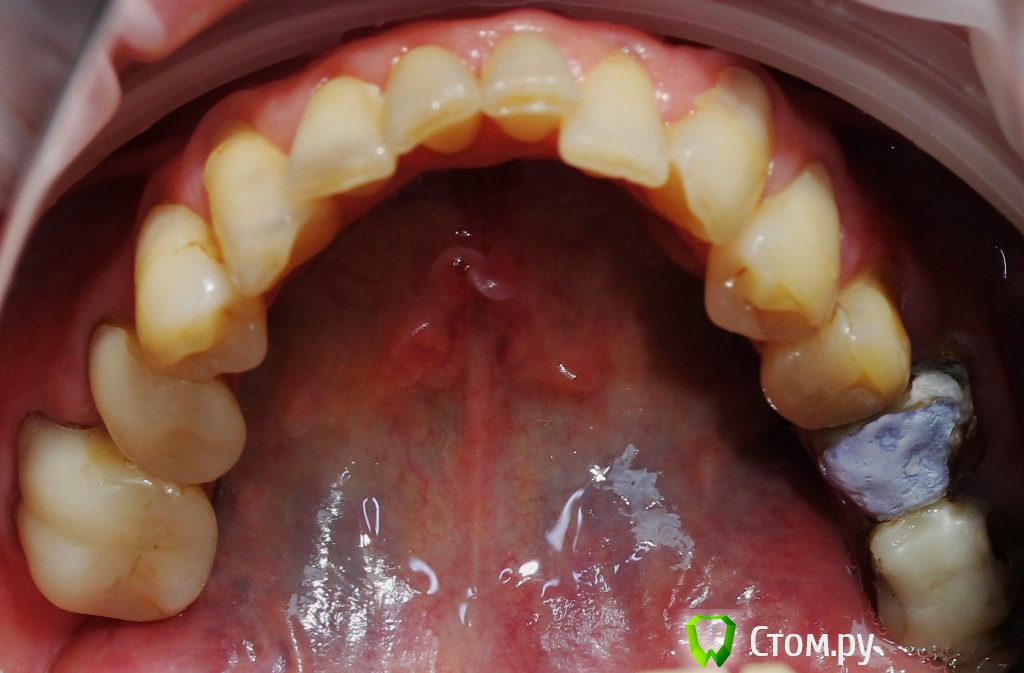

Dr.Sham Опубликовано 21 октября, 2014 Поделиться Опубликовано 21 октября, 2014 (изменено) Пациентка 55 лет с онкологией в прошлом.Аутоиммунный тиреоидит.Хочет красивые зубы, которыми можно жевать.Суставной компонент я не диагностирую, щелчков и посторонних шумов при открывании рта нет. Мышцы без гипертонуса, пальпаторно боли отмечает со стороны крыловидной медиальной и латеральной мышц слева.Фотки. Рентген. КТ пока не делал, хочется сделать с шаблоном, но пока с планом лечения не определились.Брекеты не хочет, каппы хочет, но я не знаю возможности лечения на каппах и доктора ответственного (С-Пб.) Фото: Модели в артикуляторе: ОПТГ Изменено 21 октября, 2014 пользователем Dr.Sham Ссылка на комментарий

togrul Опубликовано 21 октября, 2014 Поделиться Опубликовано 21 октября, 2014 Пациентка 55 лет с онкологией в прошлом.Аутоиммунный тиреоидит.Хочет красивые зубы, которыми можно жевать.Суставной компонент я не диагностирую, щелчков и посторонних шумов при открывании рта нет. Мышцы без гипертонуса, пальпаторно боли отмечает со стороны крыловидной медиальной и латеральной мышц слева.Фотки. Рентген. КТ пока не делал, хочется сделать с шаблоном, но пока с планом лечения не определились.Брекеты не хочет, каппы хочет, но я не знаю возможности лечения на каппах и доктора ответственного (С-ПбДобрый день, я бы провел восковое моделирование всех зубов ( Если пациентка хочет заняться всеми зубами) + кт ( потом можно сделать шаблон для хирурга) решить судьбу 38,37 удалять или нет? потом пролечить зубы, временнные коронки, имлантация + пародонтология. как регистрировали прикус? в привычном положении? Ссылка на комментарий

dnsmc Опубликовано 21 октября, 2014 Поделиться Опубликовано 21 октября, 2014 Есть такая система элайнеры (прозрачные каппы), ими лечат скученность какая имеет место у пациентки, ну опять же нужно найти хорошего ортодонта.По мимо ортодонта, тут еще надо посетить и хирурга и терапевта(удалять лечить перелечить), если же вы не все сами делаете?!Нужно КТ, а потом уже точный план лечения составить.У меня вопрос, на модели нарисованы границы, это имеется ввиду поднять десну?Ну так на оптг видно что воспаление есть, зубы на удаление как мне кажется идут например 2.6 и 3.8 хотя на модели они есть. Интерестно, что будите делать дальше, жду плана лечения Ссылка на комментарий

togrul Опубликовано 21 октября, 2014 Поделиться Опубликовано 21 октября, 2014 Есть такая система элайнеры (прозрачные каппы), ими лечат скученность какая имеет место у пациентки, ну опять же нужно найти хорошего ортодонта.По мимо ортодонта, тут еще надо посетить и хирурга и терапевта(удалять лечить перелечить), если же вы не все сами делаете?!Нужно КТ, а потом уже точный план лечения составить.У меня вопрос, на модели нарисованы границы, это имеется ввиду поднять десну?Ну так на оптг видно что воспаление есть, зубы на удаление как мне кажется идут например 2.6 и 3.8 хотя на модели они есть. Интерестно, что будите делать дальше, жду плана лечения26 можно перелечить , а вот 3.8 удалять однозначно Ссылка на комментарий